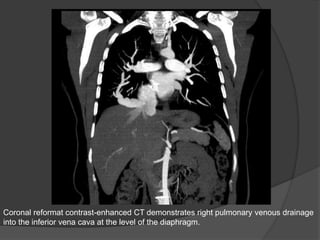

Coronal reformat contrast-enhanced CT demonstrates right pulmonary venous drainage

into the inferior vena cava at the level of the diaphragm.

Coronal reformat contrast-enhancedCT demonstrates right pulmonary venous drainage into the inferior vena cava at the level of the diaphragm.